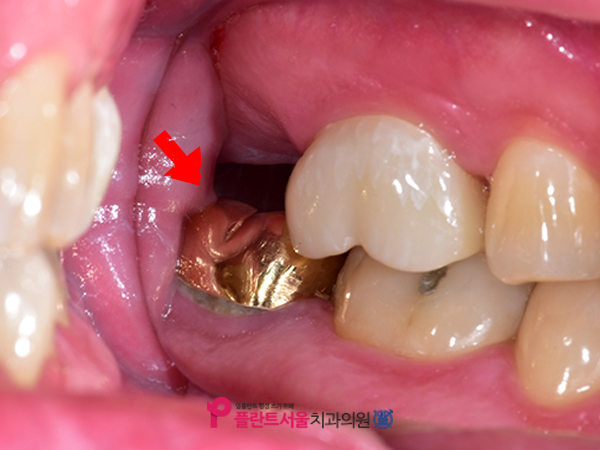

저희 병원에 처음 내원하셨을 때 찍었던 X선 사진입니다. 1년 전 위턱 제2대 어금니(#17)를 발치한 뒤 다시 이곳에 인공 치아를 심기 위해 오포치과 플랜트 서울에 오셨습니다. 환자분의 경우 꽤 오랜 기간 동안 치아가 없는 상태로 지내 왔습니다만. 이와 같이 발치 후에 장기간 그대로 두면 주위 치아가 빈 공간으로 기울어지거나 마주보는 아랫니가 위로 뻗어나와 보철을 심을 공간이 부족할 수 있으며 발치 후에는 가능한 한 빨리 인공치아를 심는 것이 좋습니다.

환자의 경우 다행히 옆에 #16번 치아가 밑에 있는 #47번 치아와 맞물려서 잘 잡고 있어서 부품을 심을 수 있는 충분한 공간이 있었습니다. 본 병원은 보다 정확한 검사를 위해 대학 병원급의 3DCT를 사용하여 환자의 구강 상태를 파악했습니다.